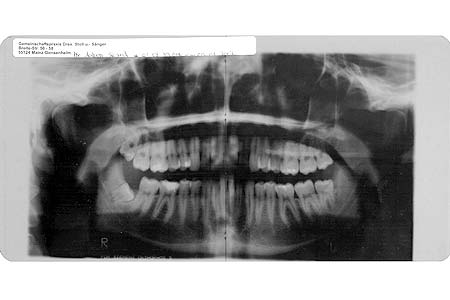

Röntgenbild 14. Januar 2002 Auch Helden haben – zumindest potentiell – Zahnprobleme. Um dem entgegenzuwirken bzw. zu profilaxieren muss man stylische Giger-eske 360°-Röntgensessions auf sich nehmen. Auch mal cool.